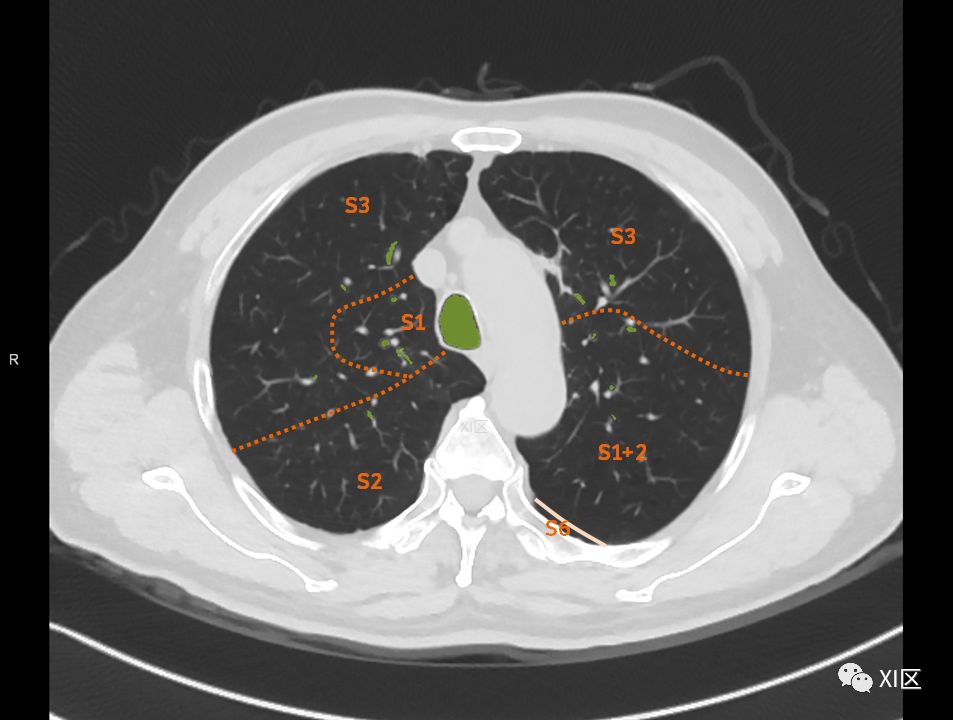

肺的断层分段示意图

在进行肺的分段时,可以上下观察浏览,沿着相应气管的走形可以更容易准确地进行分段。